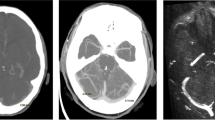

All MRI examinations were analyzed using the freely available software SEGMENT v 2.0 R5432 [16]. One examiner performed the analysis of the MRI examinations. A region of interest was drawn manually over each of the vessels in the phase image with the maximum flow. The flow was acquired by the software pixel by pixel with a temporal resolution of 30–35 slices per cardiac cycle. The same segmentation was used over the entire cardiac cycle (Fig. 1).

The arteries and veins used for measurements of cerebral blood flow and flow in the internal jugular veins. The small white arrows point at the internal carotid arteries, the large white arrows point at the vertebral arteries, and the black arrows point at the internal jugular veins. White color represents flow into the cranial cavity, and black color represents flow out from the cranial cavity. The intensity of the color represents the flow value. Note the difference in both size and flow between the left and the right internal jugular veins